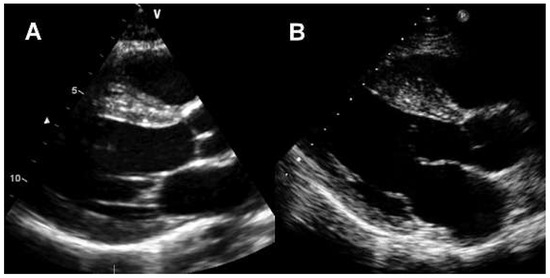

Figure 3.

Transthoracic Echocardiography. (A) West-African premier league soccer player with symmetric LV hypertrophy, interventricular septum 14 mm. (B) Caucasian leisure-time athlete with a non-obstructive hypertrophic cardiomyopathy with asymmetric LV hypertrophy, interventricular septum 22 mm.

Since HCM is one of the leading causes of SCD in young athletes, the discrimination of this pathology from athlete’s heart is clinically relevant [27,28,43]. Athletes in the “grey zone” have a LV wall thickness of 13 to16 mm. Maron et al. proposed clinical criteria for differentiating HCM from the athlete’s heart [43], that have subsequently been modified [26]. T wave inversions in the lateral leads are uncommon in athletes (Figure 1 and Figure 2) [6]. An apical pattern of LV hypertrophy or an asymmetric hypertrophy of the interventricular septum are characteristics of HCM (Figure 3). De-conditioning may resolve the aetiology of LV hypertrophy. Even after short periods of detraining (6 to 8 weeks), a resolution of physiologic LV hypertrophy will occur [44,45]. LV cavity is usually small in patients with HCM, while endurance athletes often have a LV cavity size of >55 mm [12]. Left atrial enlargement may be present in both, patients with HCM due to diastolic dysfunction and in athletes due to exercise conditioning. While athletes have a normal diastolic function, relaxation is often impaired in patients with HCM [46]. Patients with HCM have a low myocardial capillary density. Myocardial contrast echocardiography is able to measure relative myocardial blood volume and blood flow. Compared to triathletes, sedentary patients with HCM had a lower relative blood volume at rest and a lower myocardial blood flow reserve (ratio of blood flow during hyperaemia and blood flow at rest). Relative myocardial blood volume at rest most accurately distinguished between pathological LV hypertrophy and endurance-exercise induced LV hypertrophy [18]. In endurance sports, HCM is extremely rare [47], probably because the demands of competitive endurance sport, such as a supra-normal cardiac output, can hardly be achieved with the inherent impairment in diastolic filling and the low capillary density present in HCM. Therefore, patients with HCM generally have a maximum oxygen uptake of <50 ml/min/kg or <120% of the predicted maximum [48]. LV hypertrophy in female athletes is always suspicious for HCM, since only a small percentage of black female athletes exhibit a LV wall thickness exceeding normal limits [20]. A diagnostic dilemma mainly exists in the population of black male athletes, because of their high prevalence of training-induced LV hypertrophy concomitant with a high incidence of sudden cardiac death due to HCM [49]. However, only black athletes ≥16 years exhibited exercise-induced LV hypertrophy. Consequently, in black athletes, age together with the above mentioned clinical criteria may help to differentiate physiologic adaption from HCM [43]. A family history of HCM should always result in a detailed and extensive examination of the athlete, possibly including genetic testing [26]. Clinical criteria used to distinguish athlete’s heart from non-obstructive HCM are presented in Figure 4.